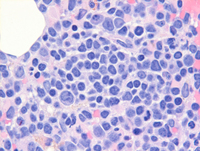

Bone marrow core biopsy

The first two images correspond to the bone marrow core biopsy from the procedure performed at the outside institution demonstrating dysplastic megakaryocytes and some background hematopoiesis in addition to increased mononuclear immature lymphoid cells.

The last image corresponds to the in-house bone marrow biopsy performed after admission demonstrating isolated lymphoid component present in a background of markedly damaged and edematous bone marrow without any background hematopoiesis.